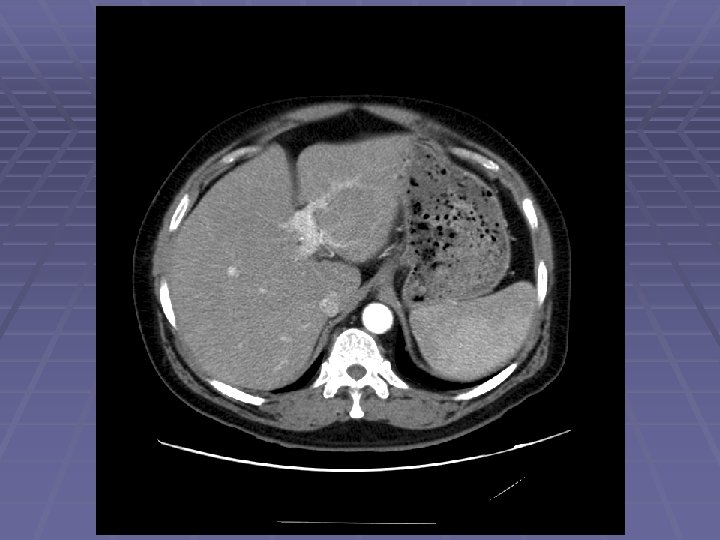

EUS Evaluation of Left Lobe of Liver